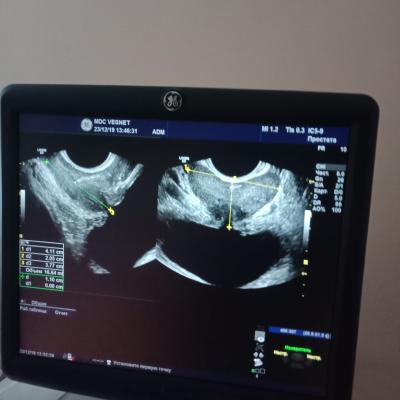

Здравствуйте, у меня такая проблема, иногда когда чихнешь или резко кашлянешь, сводит простату, иногда тянет яичко с права или скорей всего под ним, желаю узи, говорят все норм.

Здравствуйте! Сдайте эякулят на бакпосев и андрофлор. Сделайте УЗИ органов мошонки. С результатами посетите уролога очно Удачи!